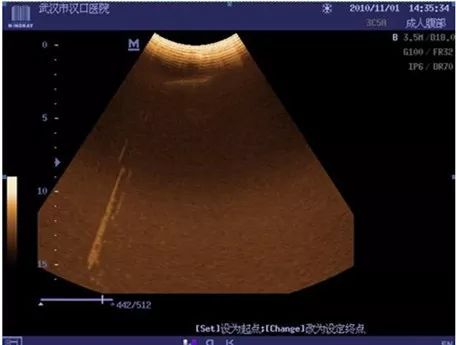

3、DC-6干扰

现象:二维图像波纹干扰;彩色取样框内条状干扰;

处理措施:更换发射板,故障解决。